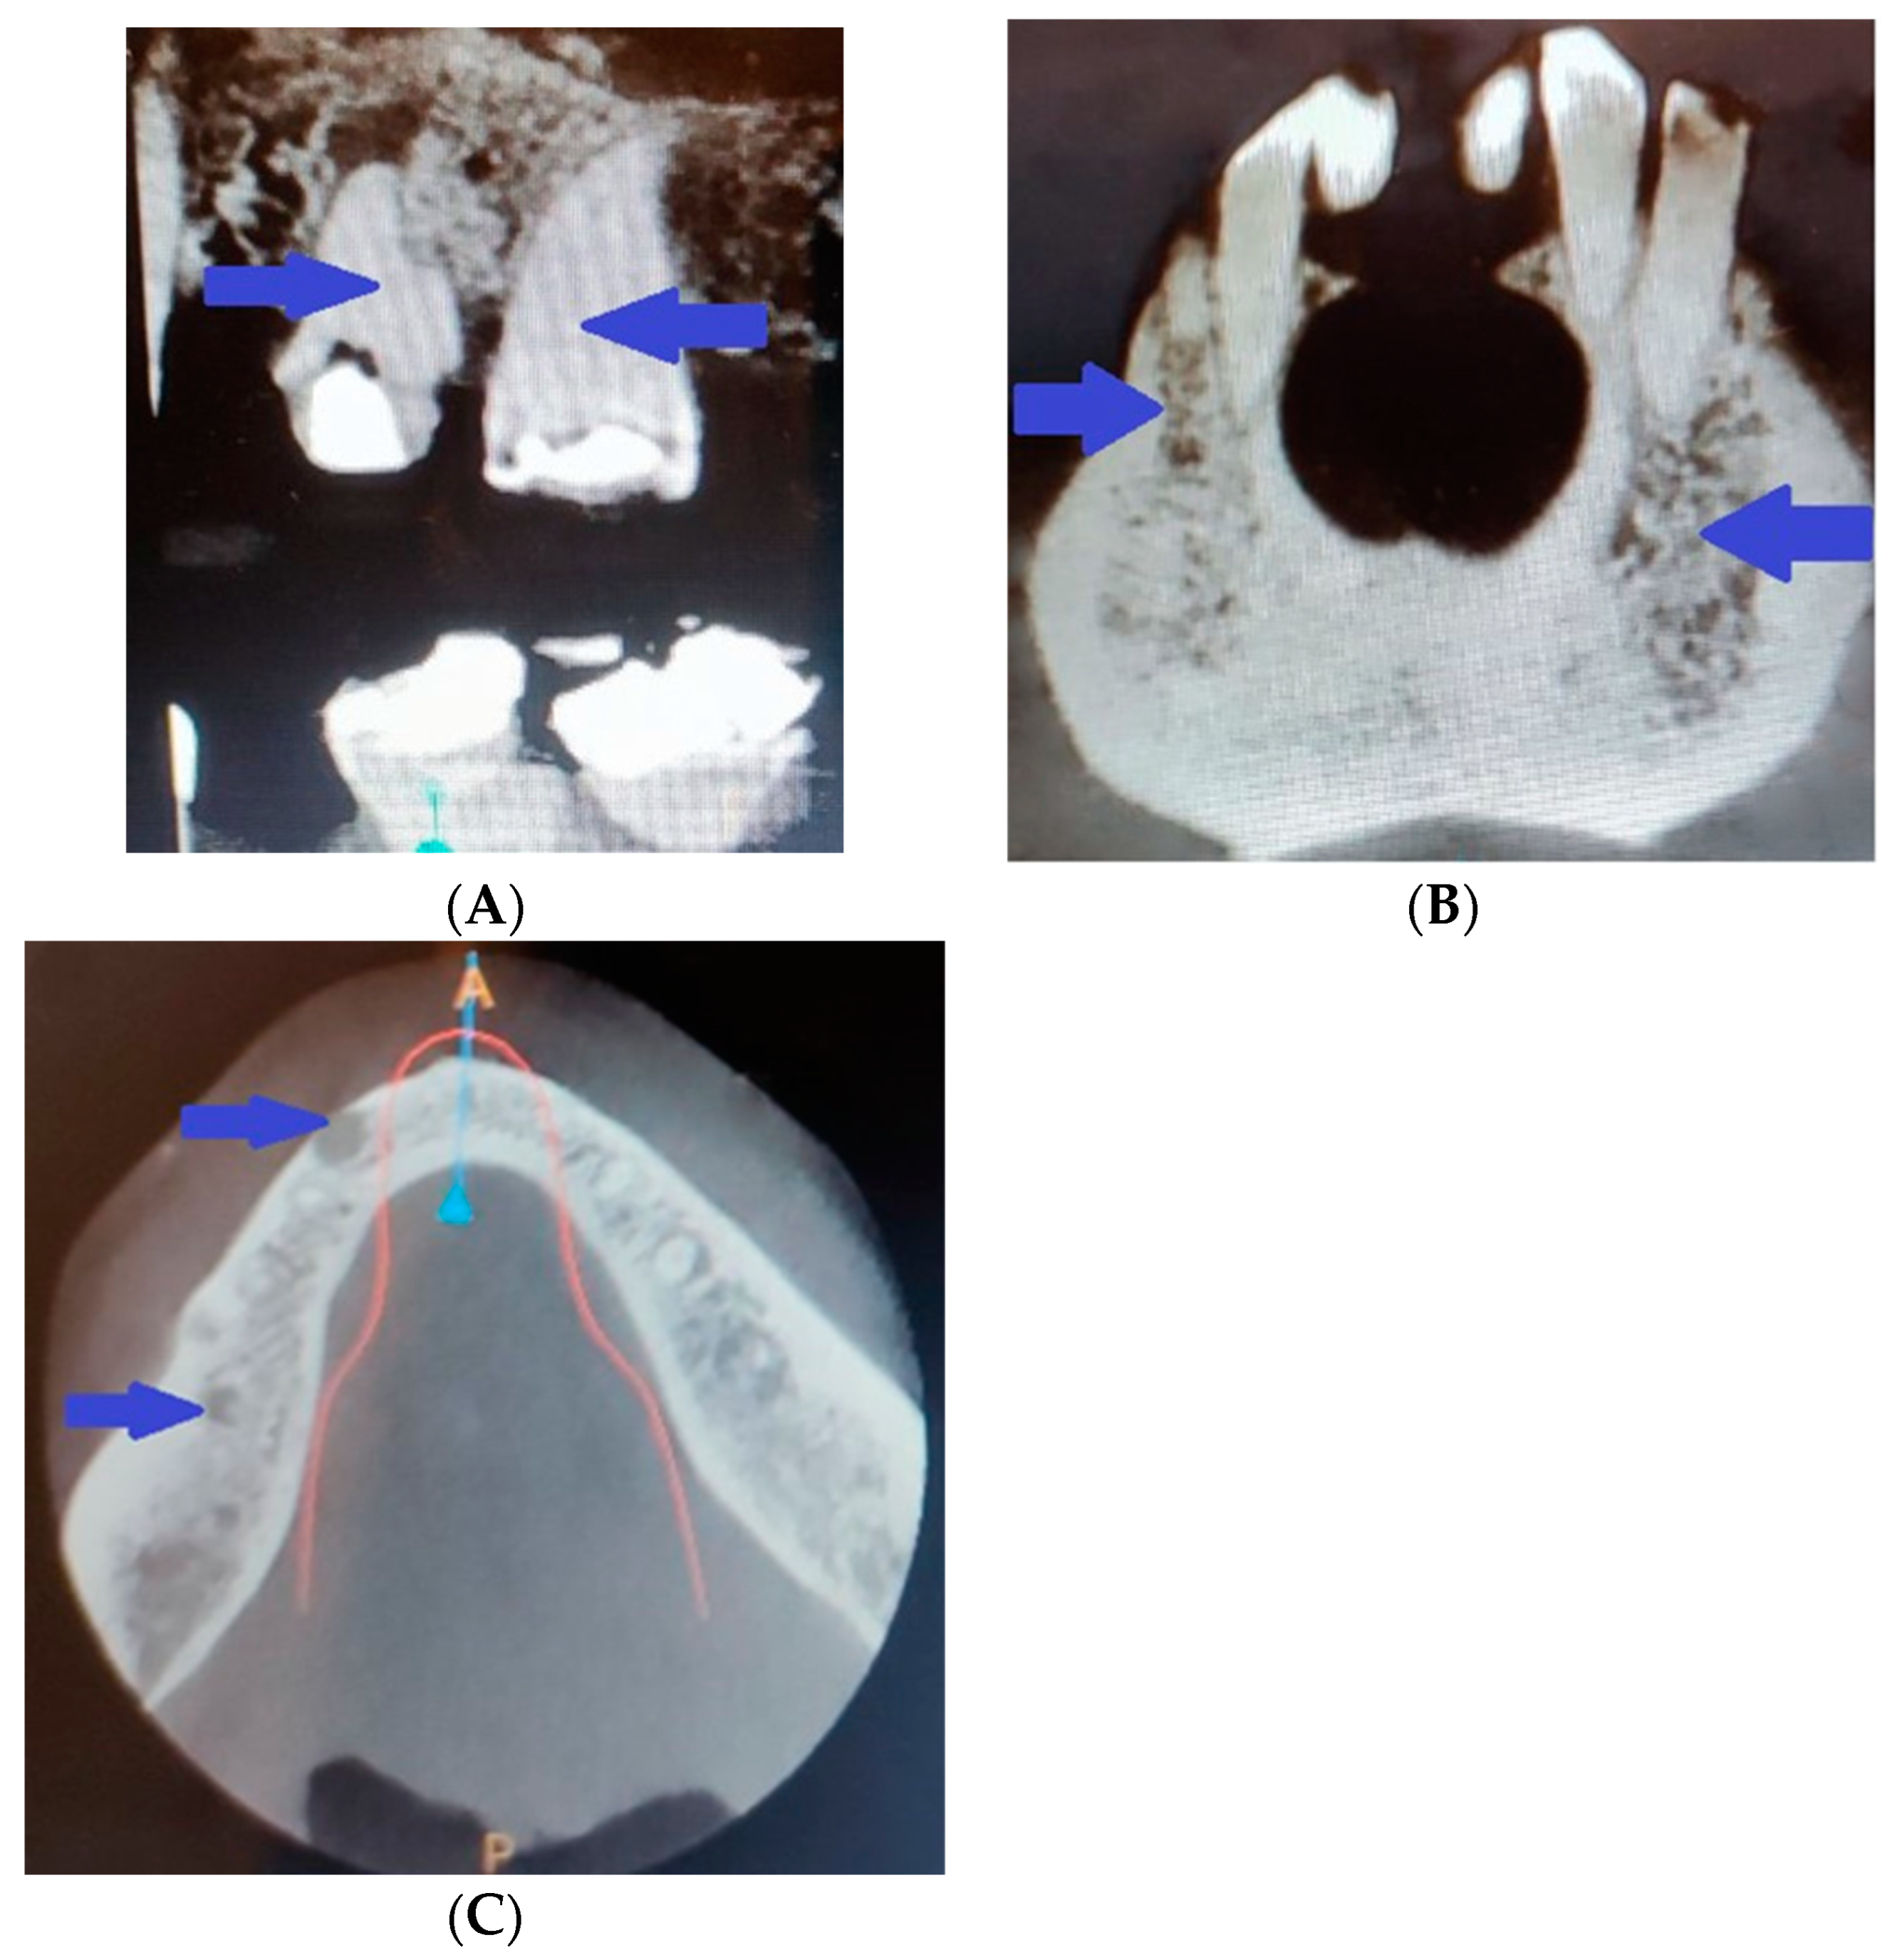

2. Clinical Case Presentation